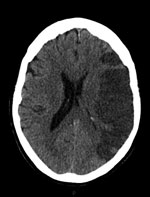

A CT scan of her brain four days after the laparotomy showed a large left middle cerebral artery territory infarct (see Figure 5). Her prognosis was discussed with her family and they were in agreement for treatment to be withdrawn the next day. The patient passed away peacefully a day after treatment was stopped. This case highlights the importance of a patient’s past medical history on initial assessment, even when it is seemingly unrelated to the proposed procedure.